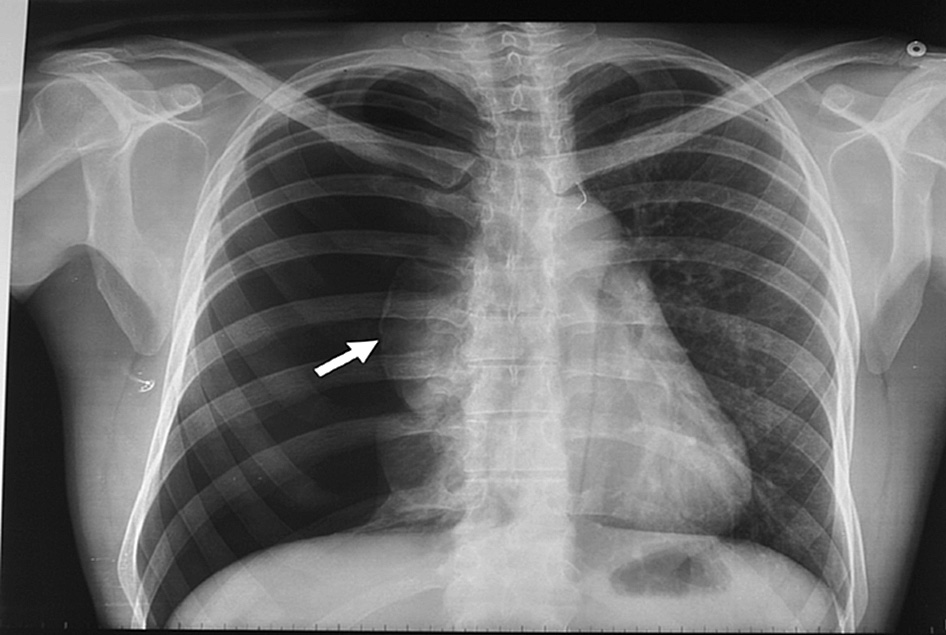

Manejo conservador del neumotórax espontáneo moderado a grande

En un ensayo clínico que comparó la intervención inicial vs manejo conservador se encontró resolución del neumotórax a las 8 semanas en 98,5% vs 94,1% de los pacientes, respectivamente. New England Journal of Medicine, 30 de enero de 2020